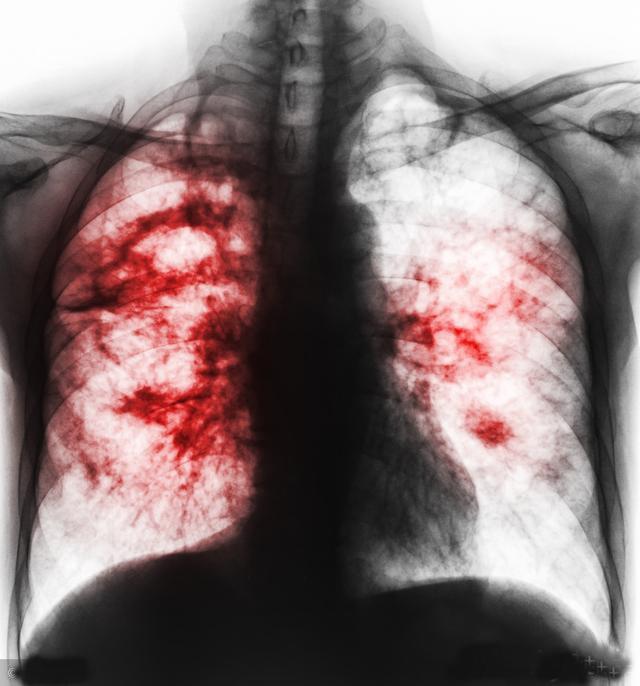

肺癌出现症状时大部分已经是瘤体比较大或者有其他部位转移了,肺癌的早期或者还没有生肺癌之前是没有什么特别能提示肺癌的症状的,而且肺癌引起的症状和其他呼吸道疾病引起的大部分症状也没有特别本质的区别,可以出现在肺癌的症状也同样可以出现在其他呼吸系统疾病中,下面我们来看看肺癌具体会出现哪些症状。

2.咯血:肺癌由于生长过快并不断的破坏周围的肺组织,很容易导致周围血管破裂出血,肺癌坏死也会有血样的物质排出,刚开始表现为痰中带血,后期可能会出现大口咯血。